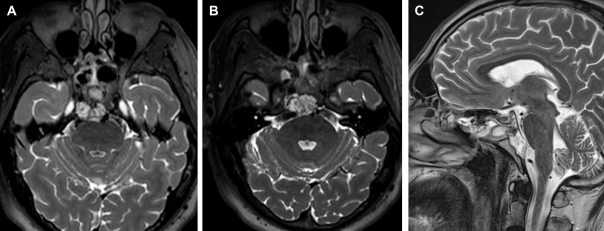

最终手术顺利完成,术后 MRI 证实肿瘤被完全切除(箭头所指为填充的脂肪),同时鼻窝保持完整。在2个月的随访中,内镜检查没有发现结痂,患者也没有抱怨任何鼻腔不适。

通过单鼻孔入路,福教授为Roger成功完成了手术,术后MRI显示肿瘤被完全切除。术中同样采用了鼻粘膜修复技术,保证了术后的生活质量。

术后MRI影像明确肿瘤全切情况,以及用于重建的自体脂肪